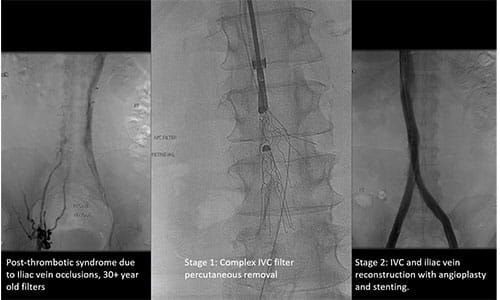

Another condition treated within the CCVC is DVT. Approximately half of patients with DVT develop post-thrombotic syndrome (PTS), experiencing symptom burden that includes leg pain, swelling, heaviness and — in very advanced cases — ulceration.

Complex IVC filter removal with IVC and Iliac Vein Reconstruction Complex IVC filter removal with IVC and Iliac Vein Reconstruction.

UH Cleveland Medical Center, with Dr. Harth as the local Principal Investigator, is participating in the C-TRACT Trial, a randomized study funded through the National Institutes of Health's National Heart, Lung, and Blood Institute (NHLBI) that seeks to determine whether catheter-assisted EVT is effective in reducing the severity of PTS in eligible patients.

“There are a number of studies that suggest there is a benefit to recanalization of the iliac vein via stent placement as compared to standard medications, compression therapy and wound care, but there is no definitive data,” Dr. Harth says. “We are excited to be the only site in our region recruiting patients for this pivotal study of PTS best-practices care.”